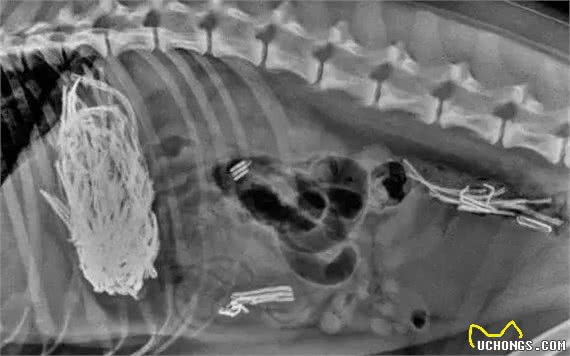

看看下面X光片照出的东西

不明三角物体

勺子

四驱车玩具

刀子

鱼钩

野草线团等